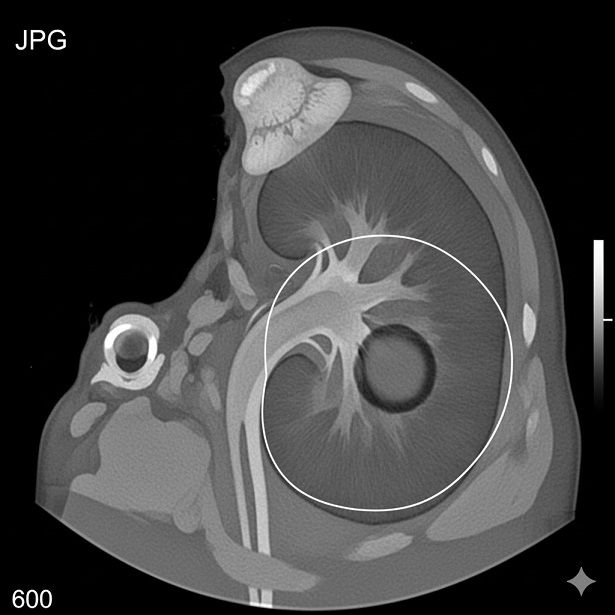

هیدرویورترونفروز چیست؟

هیدرونفروز کلیه چیست؟ هیدرونفروز کلیه (HYDRONEPHROSIS) به وجود آب در کلیه گفته می شود. در این حالت لگنچه کلیه و کالیس های کلیه که در حدود 8 تا 12 عدد می باشند، گشاد می گردند. معمولا علت، انسداد در مسیر ادرار از کلیه به مثانه می باشد و در نتیجه جمع شدن ادرار در کلیه […]